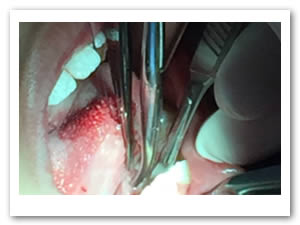

• Se realizó una incisión horizontal en la parte media del frenillo con hoja de bisturí No. 15 y mango No. 3, posteriormente se comenzó a cortar el frenillo de arriba abajo cuidando la anatomía de la región y la zona de las carúnculas sublinguales de los conductos de Wharton y Rivini. (Figuras 5 y 6).

Figuras 5 y 6. Incisión y corte del frenillo.

• Se eliminó el frenillo en su totalidad  con la ayuda de tijeras iris recta y hoja de bisturí del No. 15 así como todo el tejido residual fibroso correspondiente al frenillo. Se realizó genioplastia con pinza de mosco y disección roma para liberar adecuadamente la inserción frénica hasta la cara lingual de los incisivos inferiores. (Figuras  7, 8 y 9)

Figuras 7 y 8. Eliminación total del frenillo y genioplastia

Figura 9. Resultado obtenido después de genioplastia